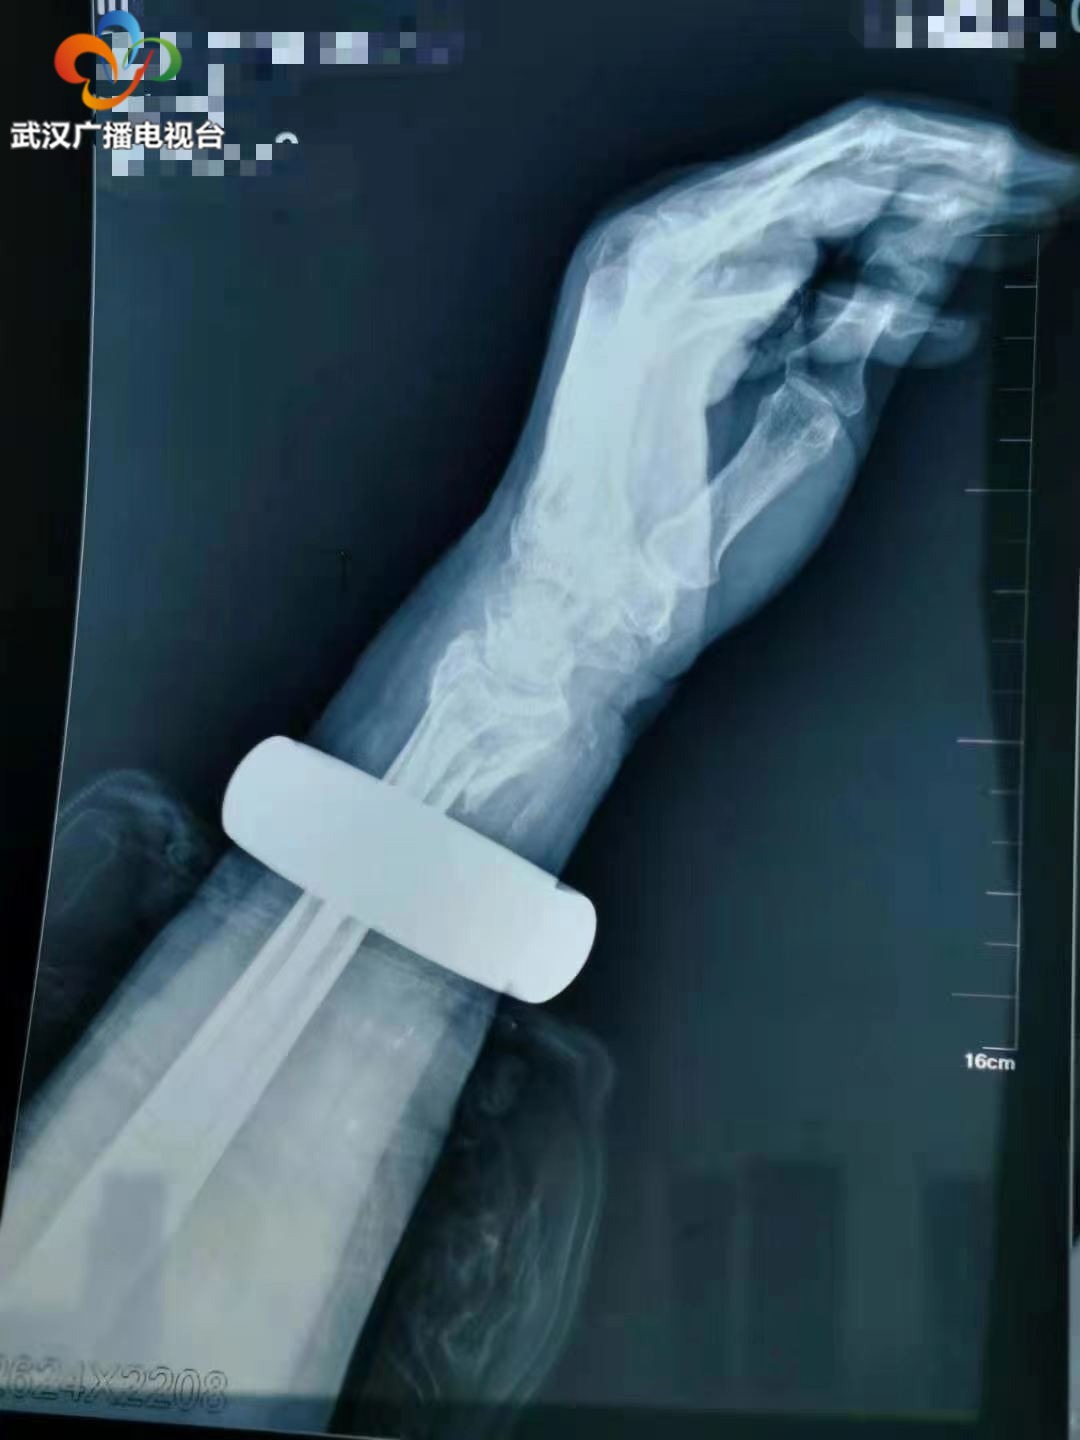

本想休息一会疼痛有所缓解,可过了近两个小时,不仅疼得不能动弹,胳膊和手腕都肿得厉害。家人见状立即将她送到武汉市第四医院手外科就诊,拍片显示,太婆左手桡骨远端、肱骨远端粉碎性骨折,需要立即入院手术。

待手臂消肿后,医生为王太婆进行手术。患者桡骨远端碎成了6块,肱骨远端碎成4块,零乱地散在四周。不仅如此,老人骨质疏松,碎骨薄如纸片无形中增加了手术难度。术中医生们像做拼图一样,找出碎骨并确定位置,除了螺钉固定以外,有些只有绿豆大的碎骨,没有合适的螺钉,就用克氏针固定,整台手术持续了3小时,目前老人恢复得不错。